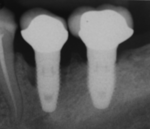

Peri-implantitis

Bone loss (peri-implantitis) on implants over 7 years in a heavy smoker

صورة شعاعية لغرسة السن.